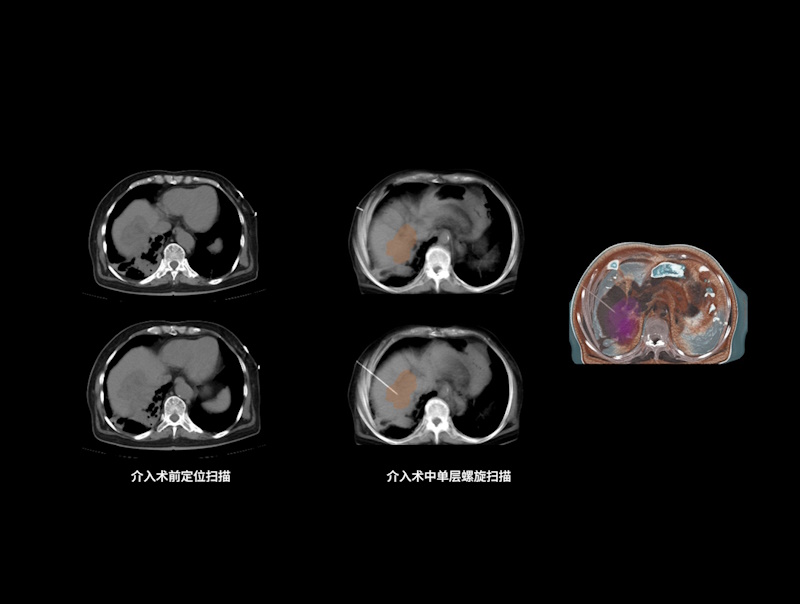

精准介入扫描方案

支持基于2D/3D进针路径精准规划,设置目标进针位置,自动计算进针路径长度和进针角度

支持单次断层扫描、单次螺旋扫描、连续断层扫描和连续透视扫描,以满足不同介入穿刺应用场景

KARL 3D双域迭代重建技术助力术后CT影像精准评估,在保证高清图像质量的同时有效降低扫描辐射剂量

提供完善专业介入套件,辅助医生床旁轻松完成病床控制、实时曝光扫描、图像浏览查看等操作